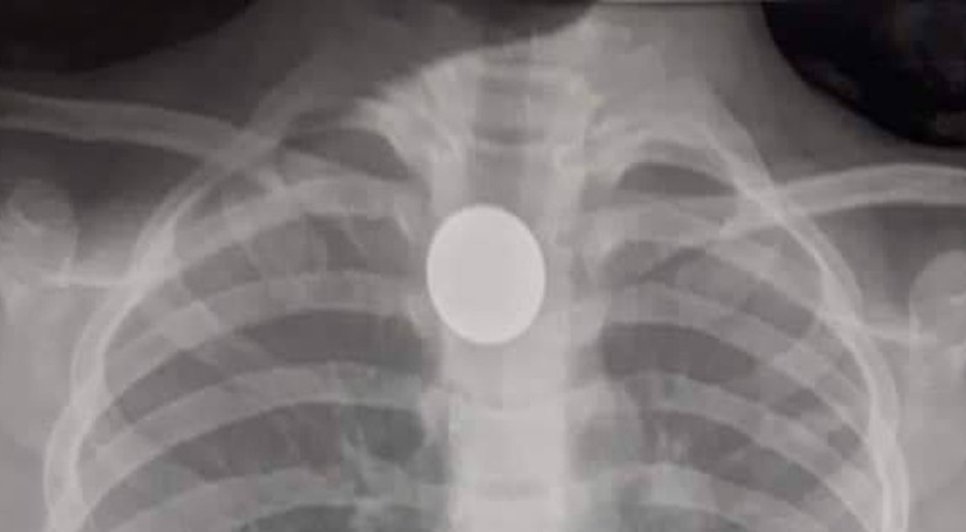

Morreu nesta quarta-feira (14), no Hospital Geral do Estado (HGE), a criança de dois anos que engoliu uma moeda em União dos Palmares, na Zona da Mata alagoana.

O menino chegou a ser internado no Hospital Regional da Mata, em União, mas foi transferida nessa terça-feira (13) para o Hospital Geral do Estado (HGE), em decorrência da gravidade da situação.